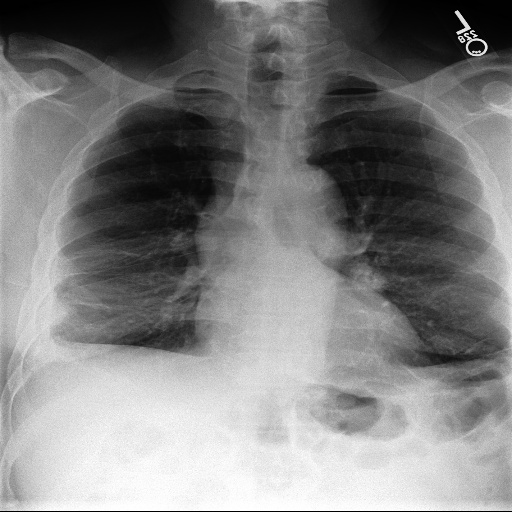

3.3 Interpretability

Post-Hoc Comparisons. We compare our concept-based explanations to post-hoc XAI techniques LIME and SHAP, applied to the baseline InceptionV3 model. The image explanations generated by these techniques disagree with each other and the medical ground truth. We show an example of this observation in Figure 7, where both techniques fail to capture the large mass in the X-ray, and highlight irrelevant regions such as areas outside of the lung as incorrectly important to the classification decision. In contrast, our approach correctly identifies the presence of a mass. More examples are shown in Figure 10.

Refer to caption

(a) Ground Truth

(b) LIME

(c) SHAP

(d) CXR-LLaVA Generated Report

(e) Our Approach

Figure 7: Example of our explanation approach outperforming LIME, SHAP and CXR-LLaVA. Ground truth (a) is a “Large right upper zone mass". LIME (b) and SHAP (c) fail to capture the mass in the X-ray. Most important image regions are bounded by yellow for LIME, and shown in more vibrant green for SHAP. CXR-LLaVA (d) generates a report which wrongly describes the image as non-cancerous. Our approach (e) correctly identifies the presence of a mass.